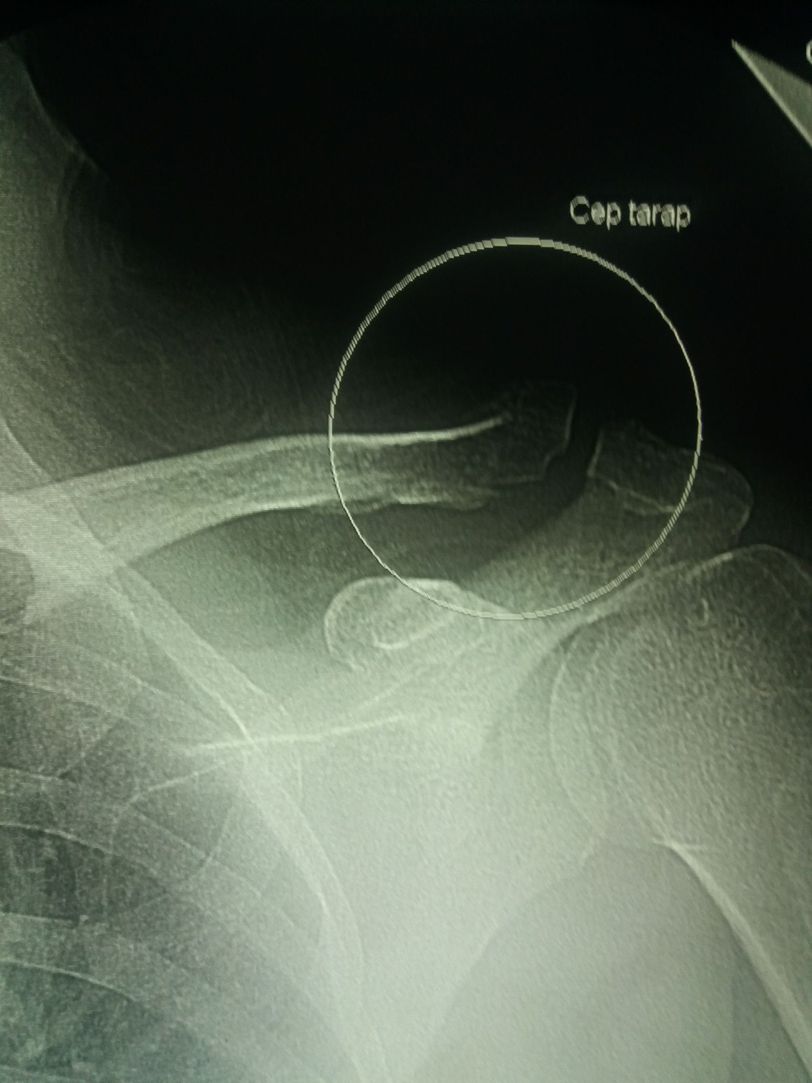

Trauma

Radiology

Clavicle